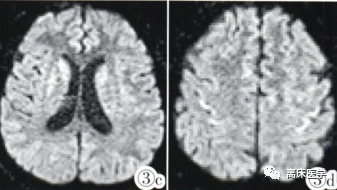

6天后复查MRI:

图:双侧尾状核.壳核及额叶皮层见对称分布T2-flair(3a,3b)及 DWI(3c,3d)呈稍高信号。

最终诊断:渗透性脱髓鞘综合征。